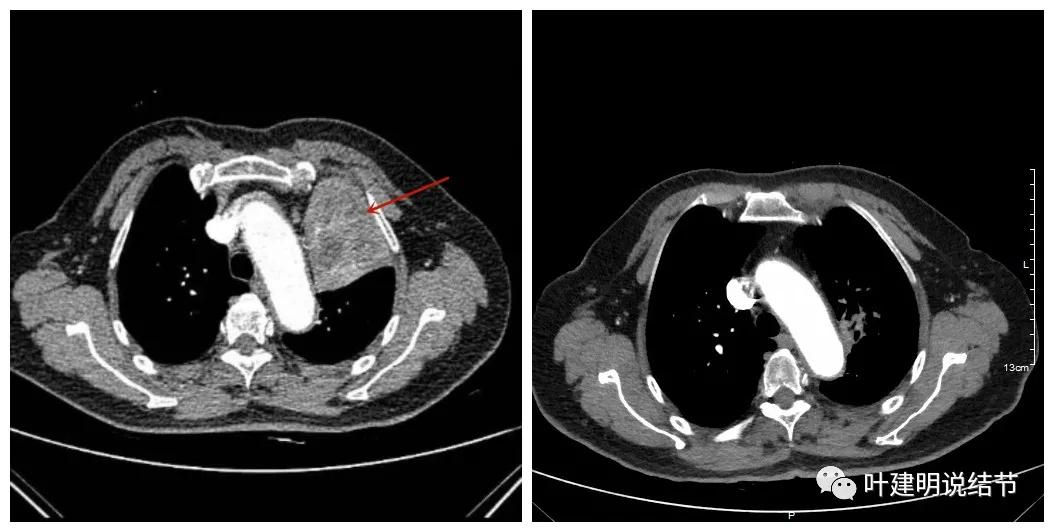

上图示肿瘤部位仍与肺动脉关系密切,似乎未能脱开,红色示肿瘤处

上图示左上叶开口已经显露出来

可见效果相当的好,如果我们把差不多同样层面的放到一起对比,更能显示化疗加免疫的惊人效果:

我样的治疗效果,显然超出了我们之前的预期,那么接下来拟选择行手术治疗,初定左上叶袖式肺叶切除加淋巴结清扫,但因为肺门区仍有软组织影,与肺动脉的关系仍密切,肿瘤与肺动脉间能否游离开来还是未知数,但至少得努力争取,鉴于患者年纪虽大,肺功能指标尚可,血气分析也基本正常,所以与患方沟通后确定行手术探查,但也也说明有万一全肺切除的可能(虽然这种可能性较小)。